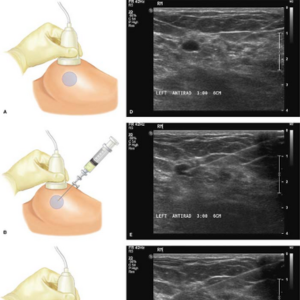

Ultrasound Guided Biopsy & FNAC

Ultrasound-guided biopsies and fine needle aspiration cytology (FNAC) are minimally invasive procedures used to collect tissue samples from organs with precision.

Image-Guided Biopsy

Ultrasound-Guided Breast/Peritoneal Collection Drainage

A precise, minimally invasive procedure to drain fluid collections in the breast or peritoneal cavity under ultrasound guidance, promoting faster healing and symptom relief.